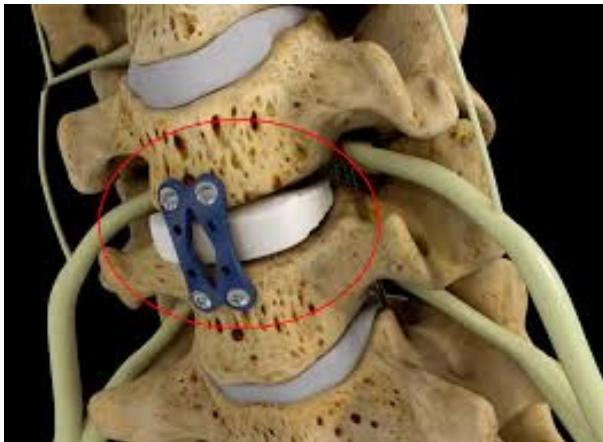

Imaging Examples:

Surgical Treatment - Anterior Cervical Discectomy and Fusion: